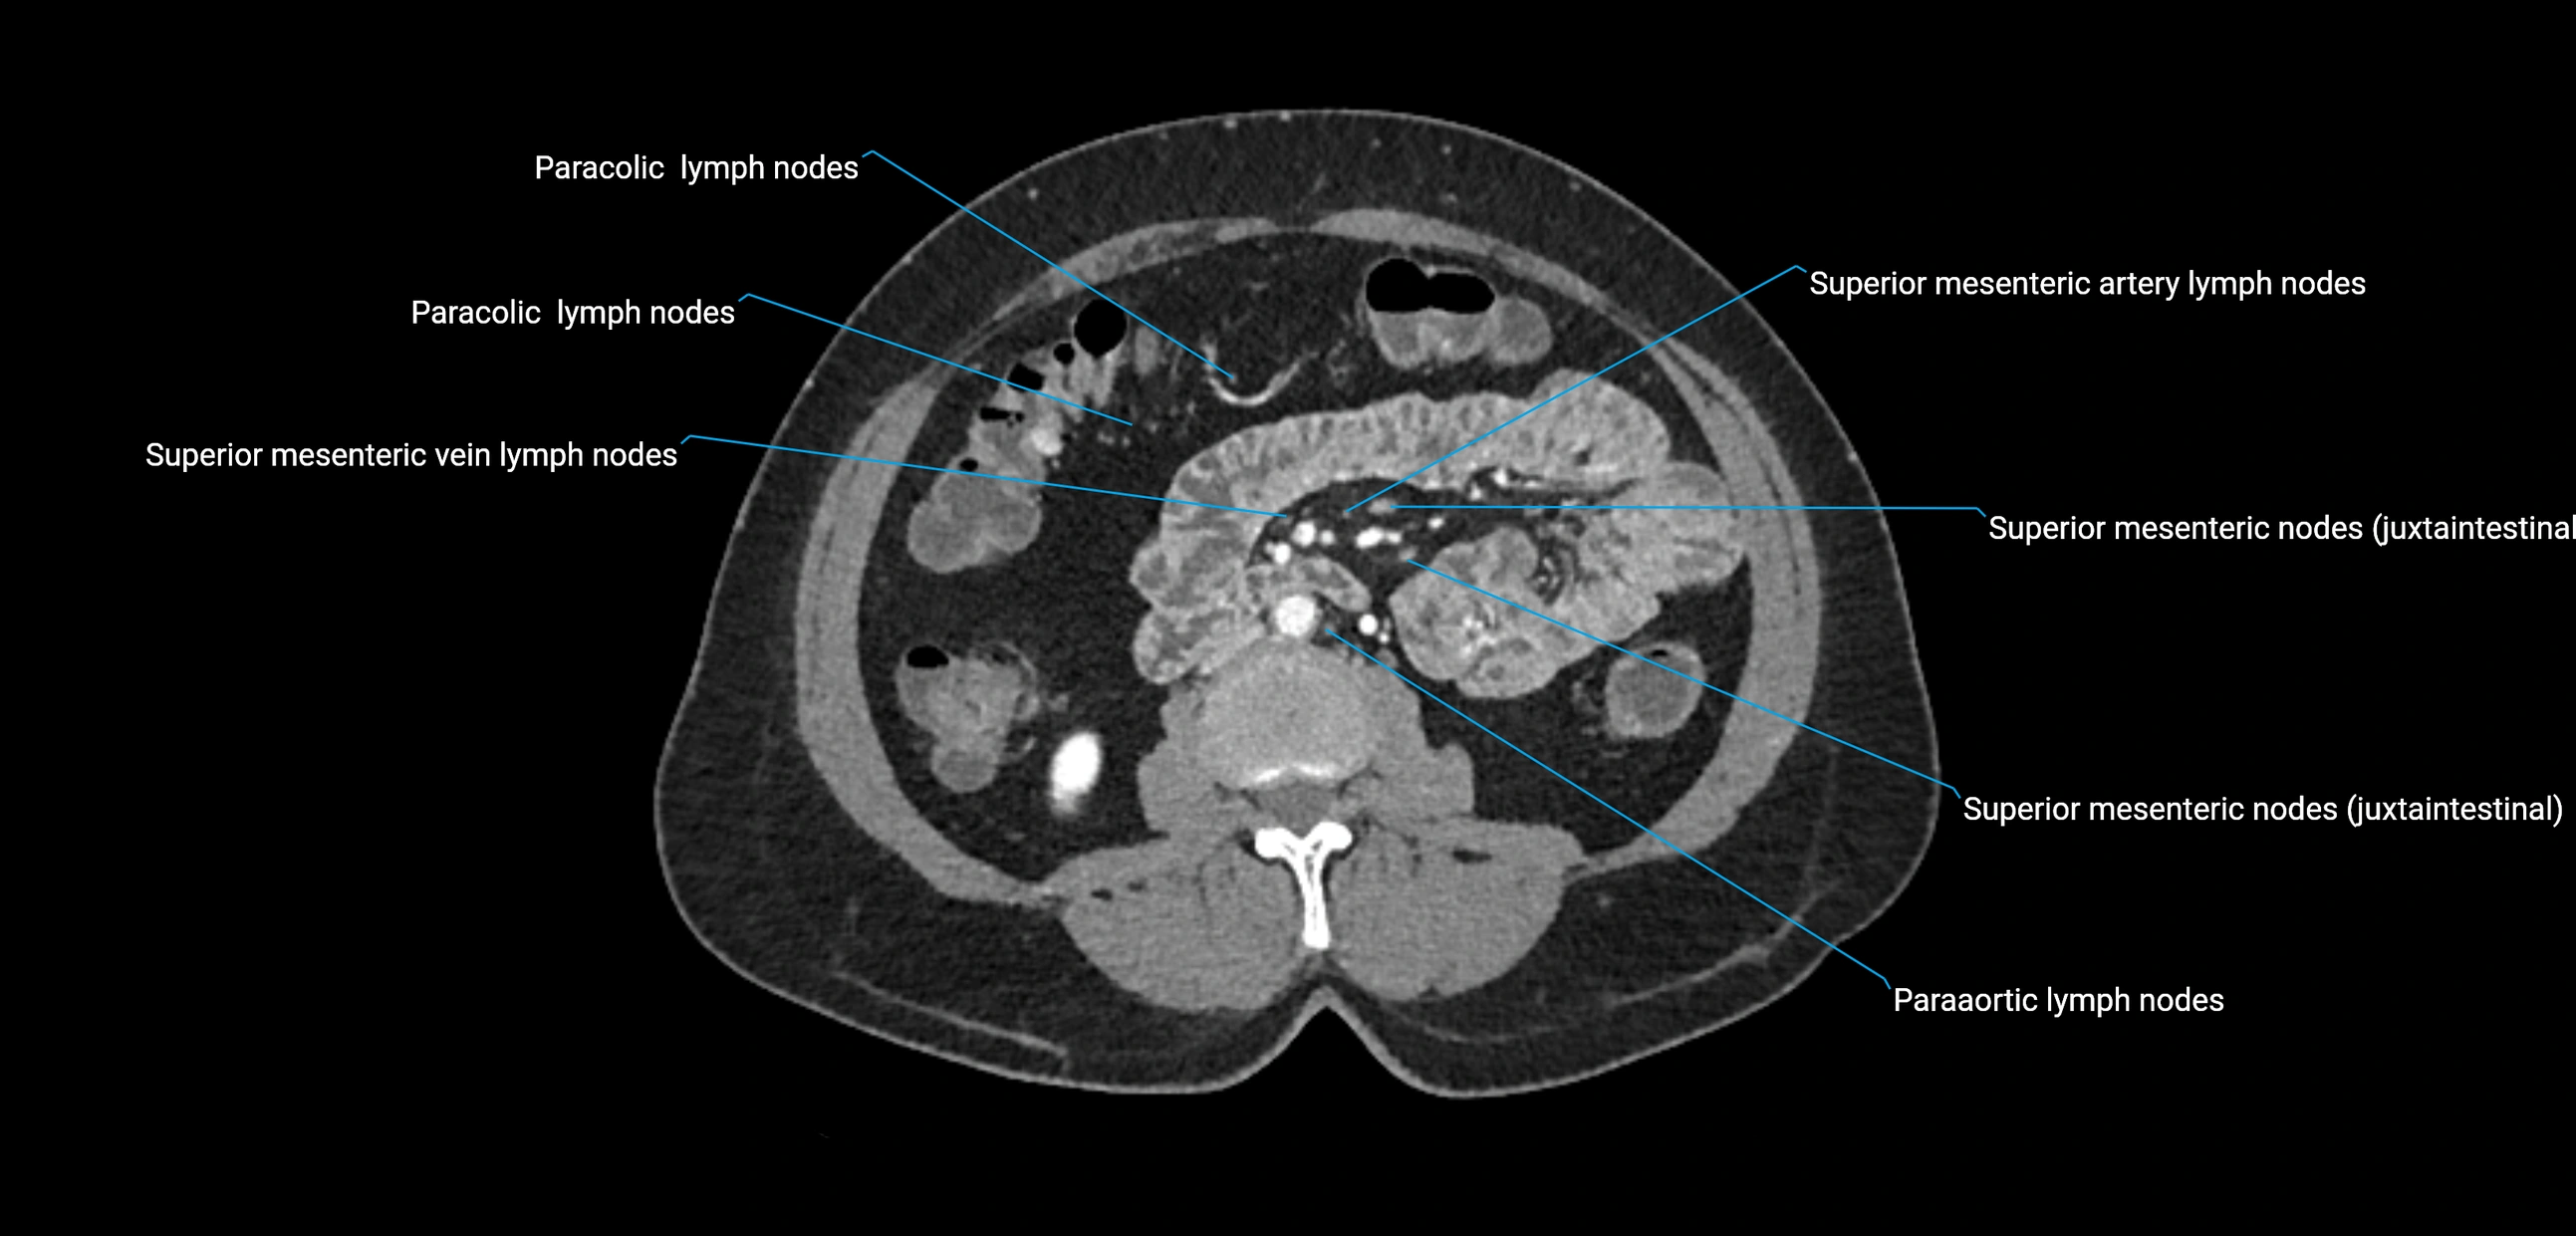

The lateral aortic lymph nodes (also called para-aortic lymph nodes) are a major group of retroperitoneal lymph nodes located along the abdominal aorta and its branches. They lie between the diaphragmatic crura superiorly and the bifurcation of the aorta at L4 inferiorly.

They are positioned on both sides of the abdominal aorta:

• Right lateral aortic nodes: adjacent to the inferior vena cava (IVC)

• Left lateral aortic nodes: lateral to the abdominal aorta

These nodes receive lymph from a wide range of abdominal and pelvic structures. Specifically, they drain lymph from the kidneys, suprarenal glands, gonads (testes/ovaries), uterus, uterine tubes, and pelvic organs, before converging into the lumbar lymphatic trunks, which terminate in the cisterna chyli → thoracic duct.

CT Appearance

CT Pre-Contrast:

• Nodes appear as soft-tissue density nodules adjacent to the aorta and IVC

• Calcification may be seen in chronic infections (e.g., tuberculosis)

CT Post-Contrast:

• Normal nodes enhance homogeneously

• Malignant nodes may show heterogeneous enhancement, central necrosis, or conglomerate formation

• Size >1 cm short axis is suspicious, though morphology and distribution are equally important

CT image

image